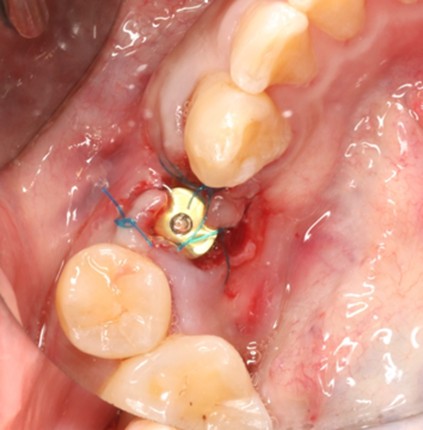

May 4, 2025: Extraction of the affected tooth.

Immediate implant placement (first-stage surgery) was performed right after tooth extraction.